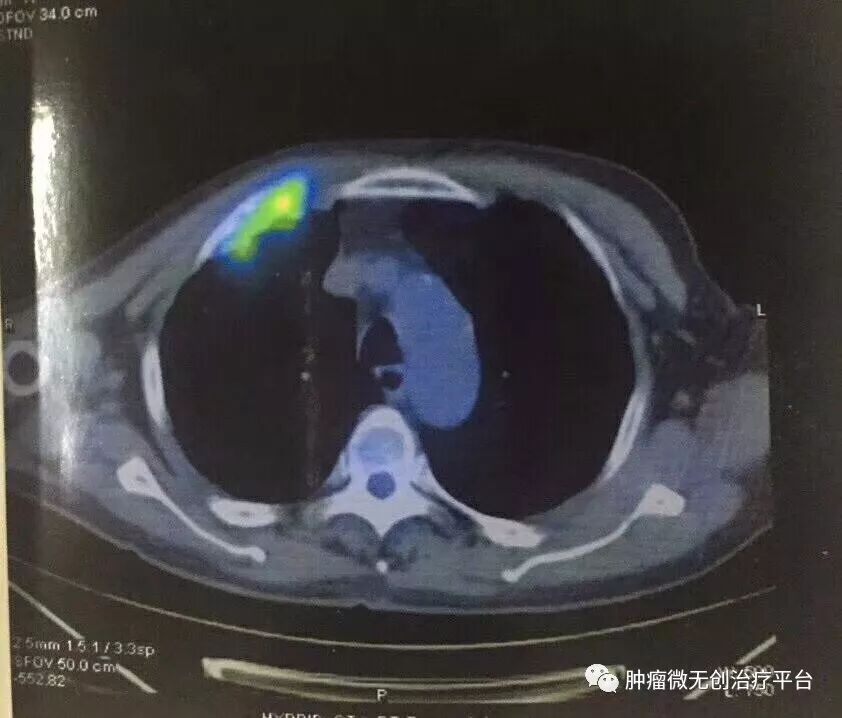

患者情况高龄(79岁)右肺腺癌侵犯胸壁患者肿瘤供血动脉栓塞➕氩氦刀冷冻消融术:图1-2术前PET-CT;图3术前CT;图4-5肿瘤供血动脉栓塞介入;图6-9氩氦刀冷冻消融治疗。